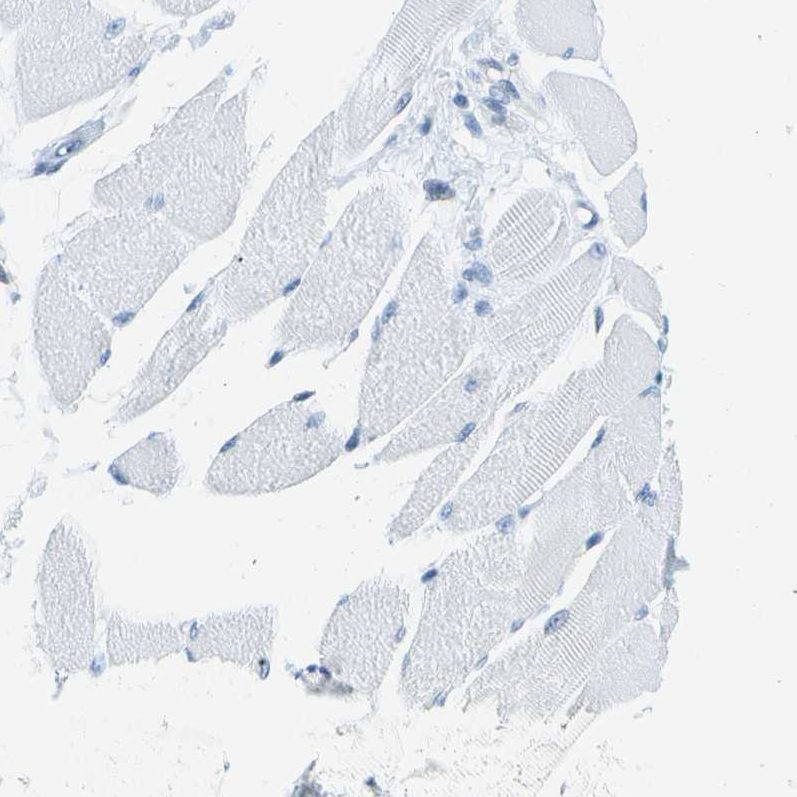

Immunohistochemical staining of human testis shows moderate nuclear positivity in cells in seminiferous ducts.